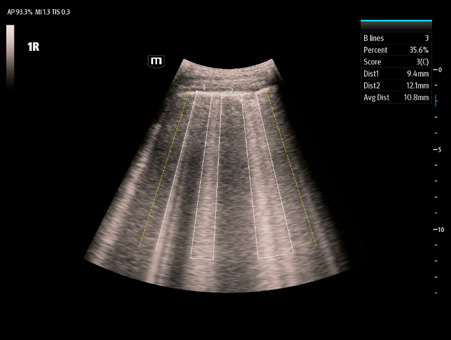

Mindray's Emergency Ultrasound Solutions address clinical challenges through a systemic approach. Those solutions cover the entire emergency care process from pre-hospital rescue and ambulance transport to ER treatment and in-hospital transfer. The versatility of Mindray Ultrasound shaping from Tablet system, Laptop-based system to Handheld Ultrasound system brings up the power of Ultrasound at the point of care. Clinical oriented smart features and protocols assist decisions with confidence.